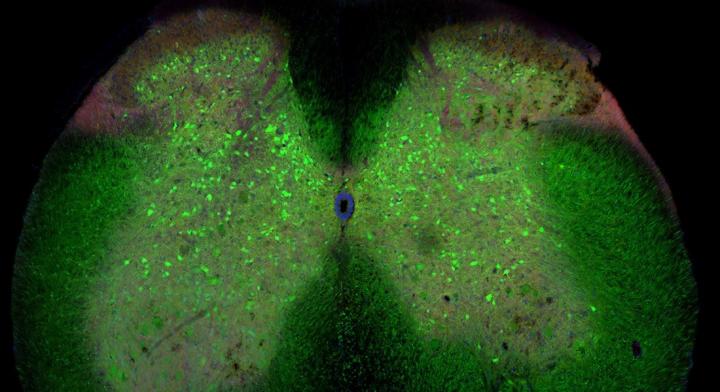

image: The spinal cord of a mouse with ALS. The green cells are inhibitory interneurons.

Ilary Allodi, University of Copenhagen